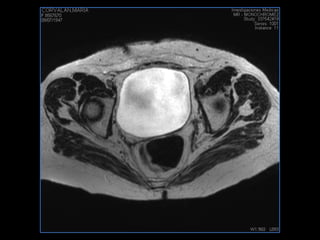

PROTOCOLO pelvis SAG T2, Y FAT SAT (FINOS) AXIAL T1  AX FAT SAT CON   GADOLINIO :  AX T1 Y COR T1 SAT: NO  FASE: RL THK: 3MM  COIL:  GAP: (FACTOR 1.4) 1MM FOV: 40 CM NEX:2 SINCRONIZACION RESPIRATORIA EN 3 O 4 CICLOS ALE

resonancia de abdomen